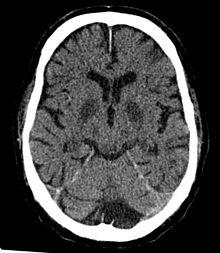

CT in a person after generalized hypoxia.

The brain requires approximately 3.3 ml of oxygen per 100 g of brain tissue per minute. Initially the body responds to lowered blood oxygen by redirecting blood to the brain and increasing cerebral blood flow. Blood flow may increase up to twice the normal flow but no more. If the increased blood flow is sufficient to supply the brain's oxygen needs then no symptoms will result.[6]

However, if blood flow cannot be increased or if doubled blood flow does not correct the problem, symptoms of cerebral hypoxia will begin to appear. Mild symptoms include difficulties with complex learning tasks and reductions in short-term memory. If oxygen deprivation continues, cognitive disturbances, and decreased motor control will result.[6] The skin may also appear bluish (cyanosis) and heart rate increases. Continued oxygen deprivation results in fainting, long-term loss of consciousness, coma, seizures, cessation of brain stem reflexes, and brain death.[7]